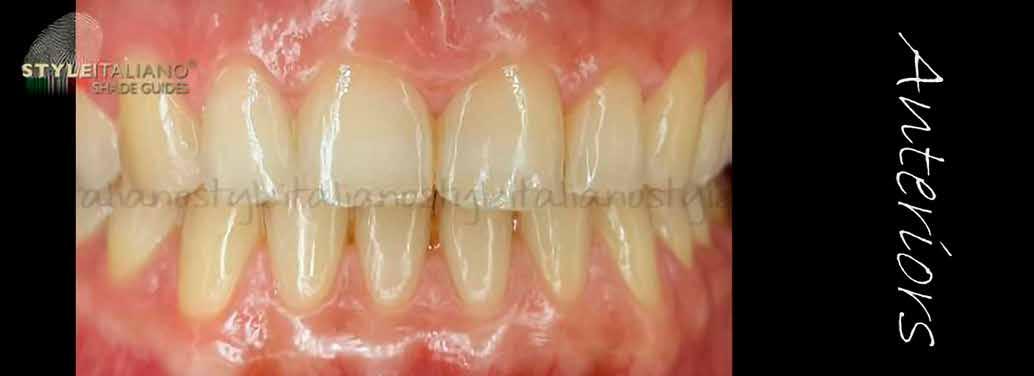

Esetbemutatás

A 19 éves hölgypáciens azzal a kéréssel jelentkezett a rendelőnkbe, hogy szebb fogakat szeretne. Az első konzultáció alkalmával megkérdeztük, hogy mi zavarja leginkább a fogazatának jelenlegi megjelenésében, valamint azt is megbeszéltük vele, hogy milyen végeredmény elérése esetén lenne maradéktalanul elégedett. Ebben az esetben a kezelési célokat az alábbiakban határoztuk meg:

A páciens fogazata esztétikai megjelenésének és funkcionális működésének a lehető legtöbb, saját foganyag megtartása mellett történő helyreállítása (1. és 3. ábra). A lehető legideálisabb esztétikai végeredmény elérése érdekében néhány esetben a fogak alakjának módosítá -

sára is szükség van (2. és 4. ábra).

A kezelés megtervezése során kifejezett jelentősége van annak, hogy jó kommunikáció legyen a páciens, a fogorvos és a fogtechnikus között. A páciens leendő fogazatának természetes megjelenését a kezelésben részt vevő team szakmai felkészültsége, gyakorlati tapasztalata és a kezelés sikerességének irányába történő elkötelezettsége biztosítja. A beavatkozások megkezdése előtt megtörtént a páciens anamnézisének a felvétele, valamint a klinikai kivizsgálását is elvégeztük. Ezt követően lenyomatokat készítettünk a kiindulási állapotról, majd a kiindulási helyzetet extra- és intraorális fotók segítségével is rögzítettük (13. a-c. ábra).